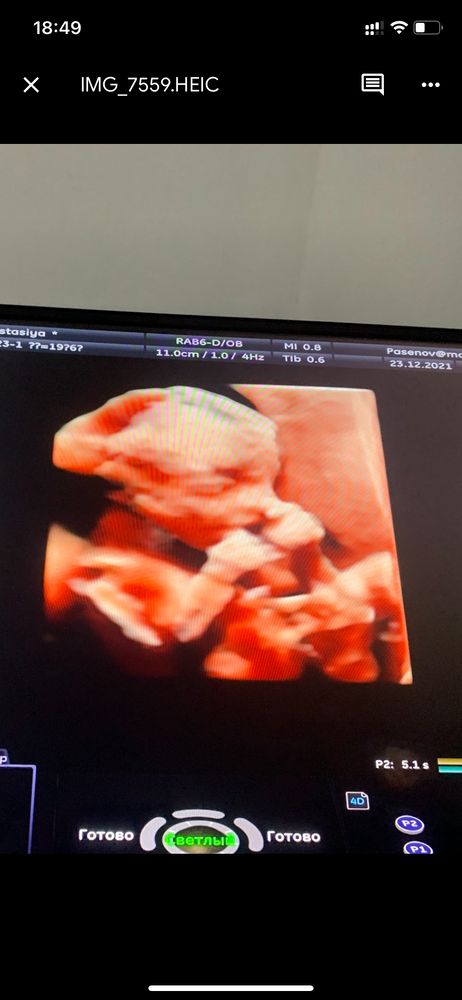

Делала 3д в 21 неделю - жутенько выглядело, если честно 😅 Гуманоид такой непонятный. В 29 недель уже красивый ребёночек визуализировался. Пока нет жировой прослойки на лице - о понятных чертах лица сложно говорить. А она недели в 24 только появляться начинает

Если прям человека хотите посмотреть, то с 28 недель. В 16 недель там действительно делать нечего, малыш еще на гуманоида похож 🤣. Но пол посмотреть можно и в 16. Я сейчас кину вам фотки в 16 и в 20 недель 3д

Вчера делала, 25нед3дня

Тем не менее все хорошо видно, оч на мужа похож 🙈🙈🙈

Если черты лица, то 26-28: уже и щечки будут, и губки.